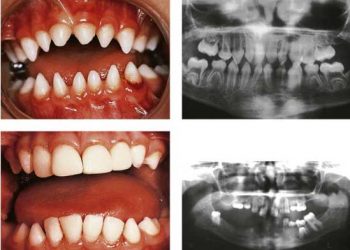

Yalancı Az Dişilik, embriyonal dönemde normal olarak gelişen kimi dişlerin alveoler kemik içinde gömülü kalması ve diş sayısında görünüşte bir...